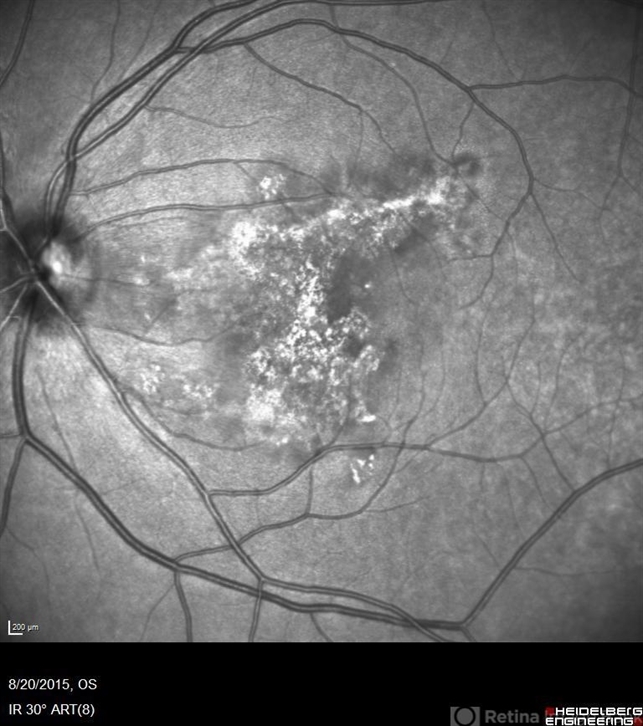

- macula serpiginous choroidopathy

- Phylicia Yanna, Retina Eye Center, Eye Associates of Northeast Louisiana

- Heidelberg Spectralis

- Red free photograph of an 18-year-old with macular serpiginous choroidopathy.